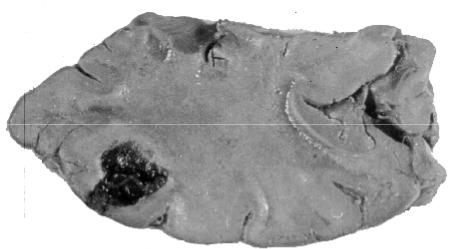

Чаще всего контузионные очаги располагаются на выступающих поверх- ностях мозга, на гребнях извилин, вплотную прилегающих к внутренней поверх- ности костей мозгового черепа. Макроскопически (рис. 56) они представляют

собой участки геморрагического размягчения ткани мозга с кровоизлиянием в субарахноидальном пространстве. Они несколько выбухают над поверхностью мозга. Если мозговые оболочки оказываются разорванными, то в местах разрыва выбухает мозговой детрит. Через сутки после травмы контузионные очаги обыч- но приобретают кашицеобразную консистенцию. В случае смерти через 3 — 4 недели после травмы они оказываются запавшими, ржаво-коричневого цвета.

Рис. 56. Макропрепа-

рат головного мозга при его ушибе: контузионное повре- ждение очаговый некроз и кровоизлия-

ние в коре головного мозга